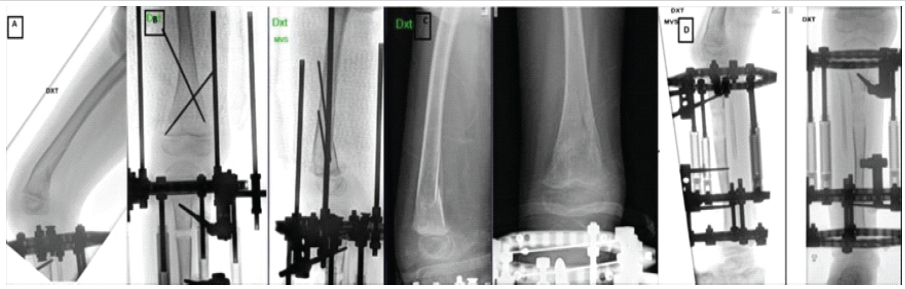

To correct the LLD, the patient underwent lengthening surgery of the short lower limb on the unaffected side with a circular external fixator. A low-energy proximal tibial osteotomy was performed, and an ostectomy of the fibula was made, and at the same time, both the proximal fibula and the distal fibula were fixated to the tibia with transosseous wires (Fig. 2). No surgery was performed on the femur, and the external fixator did not include the femur. Three weeks after surgery, the patient had a non-traumatic femoral fracture on the operated side (Fig. 3a). Given the absence of significant trauma and the presence of NF1 and MEK inhibitor therapy, the fracture was considered pathological. Management included plaster casting and K-wire fixation (Fig. 3b). Four weeks after fixation, plaster and K-wires were removed (Fig. 3c and d). Lengthening process resulted in a 4 cm gain, equivalent to 17% of the original tibial length (4/24 cm). Approximately 2 months after hardware removal, a refracture of the femur occurred at the same site (Fig. 4a), which was again treated with K-wire fixation and plaster (Fig. 4b).

Figure 2: Anteroposterior and lateral radiographic views of the right lower limb during tibial lengthening using a circular external fixator.

Figure 3: (a) Fracture of right distal femur (b) Anteroposterior and lateral radiographs showing k-wire fixation following femoral fracture during limb lengthening (c) Fracture healing, after 4 weeks of fixation (plaster and k-wires removed) (d) Lengthening process during the same period.